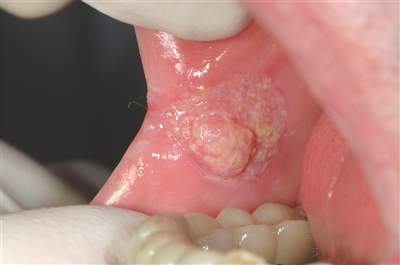

Dấu hiệu cảnh báo ung thư miệng

Có bất kỳ điểm sùi hoặc loét nào ở lưỡi, niêm mạc má, lợi đã điều trị 2 tuần mà không khỏi.

Trong miệng hoặc trên môi có các điểm, nốt màu đỏ, trắng.

Bị sưng tấy hoặc nổi một u ở bất kì điểm nào trong miệng hoặc ở cổ.

Cảm thấy khó khăn, trở ngại trong việc nói và nuốt hay có những tổn thương bị tái phát nhiều lần trong miệng.

Bị tê dại hoặc mất cảm giác ở bất cứ điểm nào trong miệng.